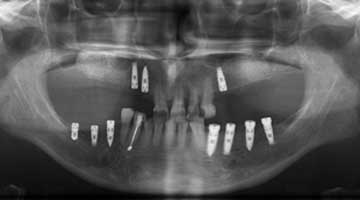

The third article is titled “Peri-implant Hard and Soft Tissue Stability in Implants Placed Simultaneously Versus Delayed with Intraoral Block Bone Grafts in Horizontal Defects: A Retrospective Case Series Study.” In this retrospective case series, investigators from the University of Valencia, Spain, compared the three-year outcome of dental implants placed simultaneously or delayed with intraoral onlay block bone grafts before or at implant placement between 2005 and 2010. The parameters evaluated at follow-up visits were implant survival and success rates, peri-implant soft-tissue conditions (Plaque Index and Bleeding Index, probing depth, width of keratinized mucosa, and facial mucosal retraction), radiographic peri-implant marginal bone loss, and patient satisfaction. Thirty-four patients with 53 implants (23 delayed and 30 simultaneous) were included.

After three years of loading, the cumulative implant success rate was 83.3% for simultaneous and 96.9% for delayed implants (P = .217). Average marginal bone loss was 1.15 ± 1.67 mm for simultaneously inserted implants and 0.29 ± 0.35 mm for delayed implants (P < .01). There were no significant differences in Plaque Index or modified Bleeding Index between the groups. Peri-implant facial mucosal recession was more frequent in the simultaneous implant group (26.6% vs 13%), though the difference was not statistically significant. General patient satisfaction averaged 9.05 ± 0.82, and good quality of life was reported by all patients.

The authors concluded that despite its sample size and design limitations, the delayed procedure showed less marginal bone loss and a lower prevalence of facial mucosal recession than the simultaneous implant placement procedure at three years post-loading.